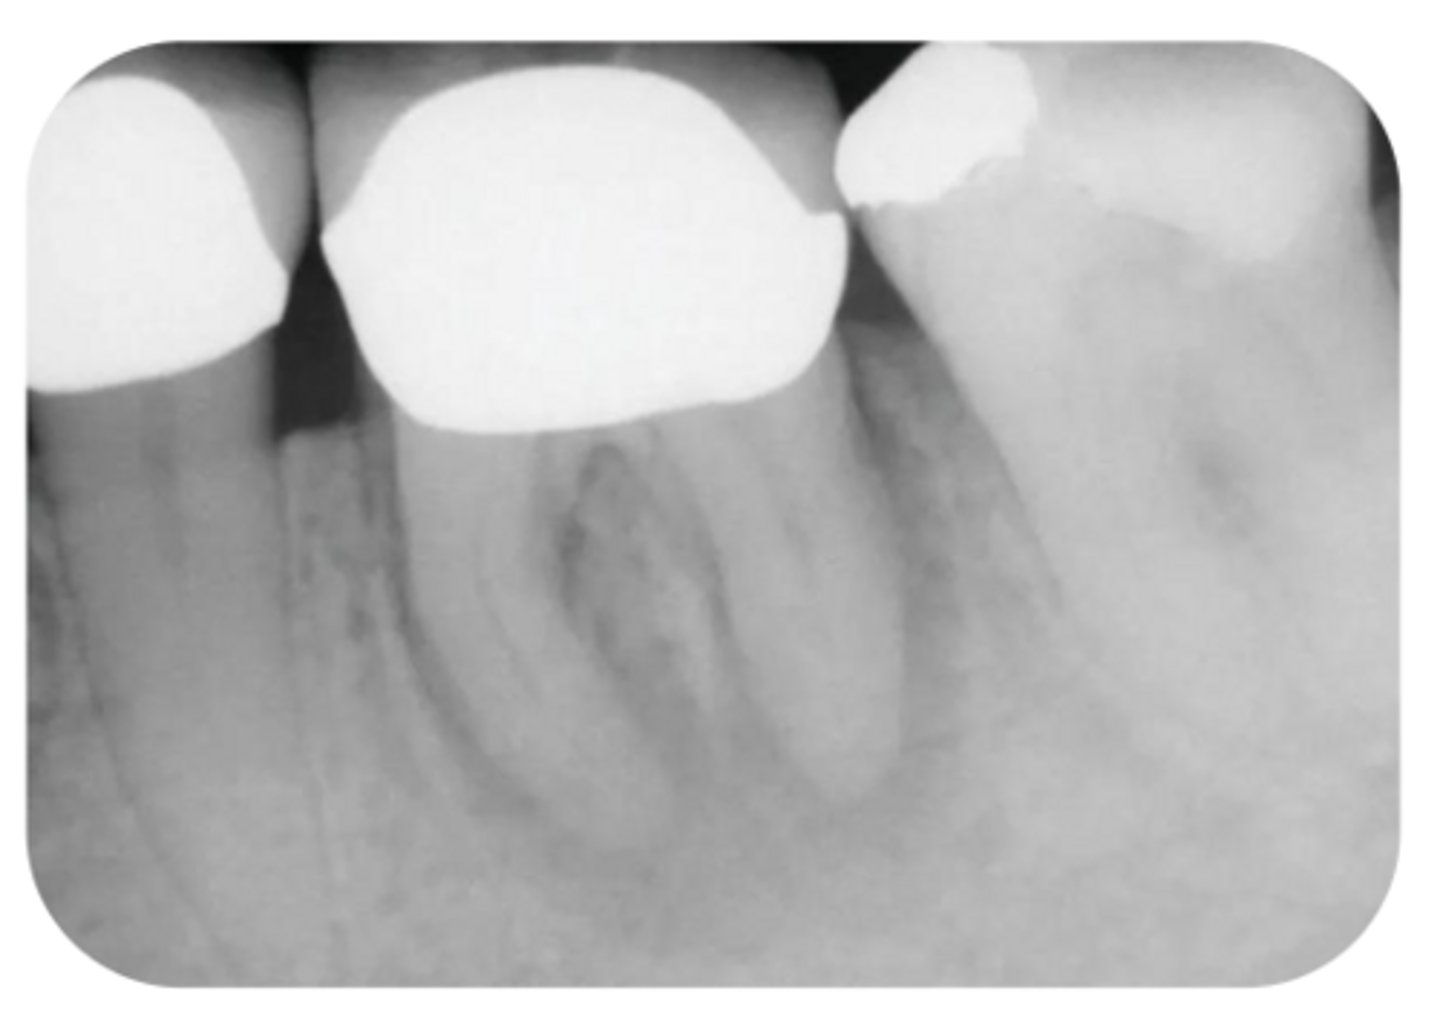

What are the radiographic findings on #3?

- M Caries

- Pulp stones

- Pulp chamber receeded